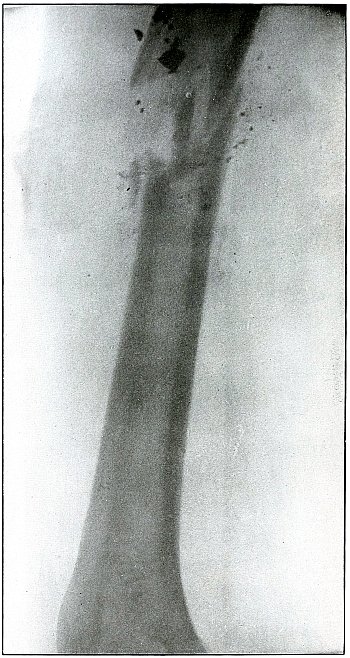

| 47. |

Gunshot wound, gluteal region |

104 |

| 48. |

Gunshot wound, thigh |

106 |

| 49. |

Gunshot wound, thigh |

108 |

| 50. |

Gunshot wound, thigh |

110 |

| 51. |

Gunshot wound, thigh |

112 |

Rifle—Plate 48.

LOWER EXTREMITY.

Gunshot Wound of the Thigh,

with Lodgment of the Bullet.

Wound of entrance, outer aspect of the thigh at the junction of the

upper and middle thirds.

The slight penetration without bone injury and with slight deformity

of the nose of the bullet indicates that the wound was caused by a

ricochet shot at extreme range, after its energy was almost spent.

With the posterior aspect of the thigh next to the plate, the dense

shadow and the nearly normal size of its outline indicate that the

bullet was in the same relative position and that it lay posterior to

the neck of the femur.

As such wounds are rarely infected, the treatment is conservative,

and a search for the missile is only justified by serious infection,

pain, or impaired function.